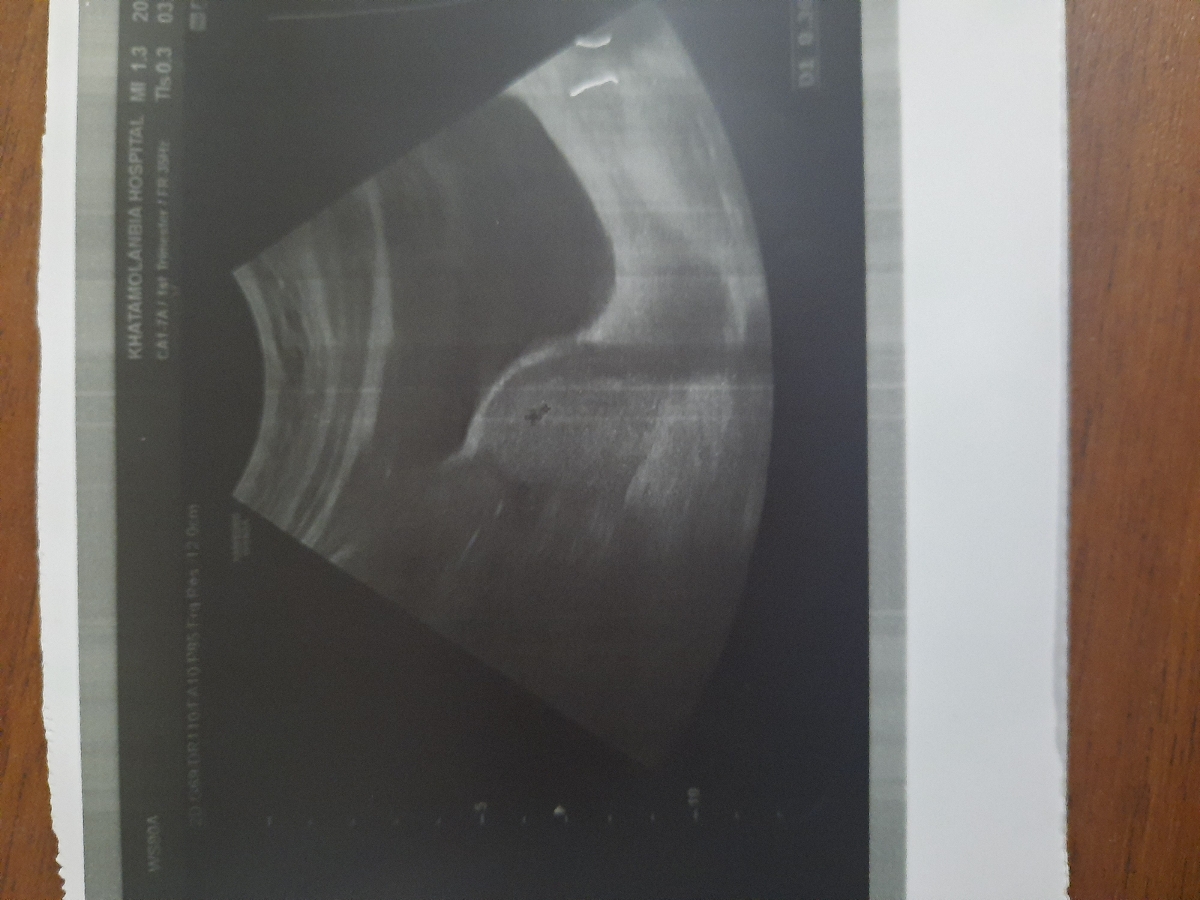

عزیزم چقدر زود رفتی ، نه ساک دیده شده نه ضربان ، آخه پنج هفته خیلی زوده

خیلی زود رفتی فعلا چیزی تشکیل نشده گلم😍🌈

دوهفته دیگه سونو رو تکرار کن

البته تو سونو نوشته یه هفته دیگه تکرار کنی اما بازم زوده خودتو تقویت کن چون مغز و قلبش تشکیل میشه

اتفاقا سونو رو کار خوبی کردی رفتی بخاطر خارج و داخل رحم ولی دیگ نرو تا هشت هفته

قلبشم تشکیل میشه تو هشت هفته

سلام فعلا زود است دو هفته دیگه مجدد سونو را تکرار کن